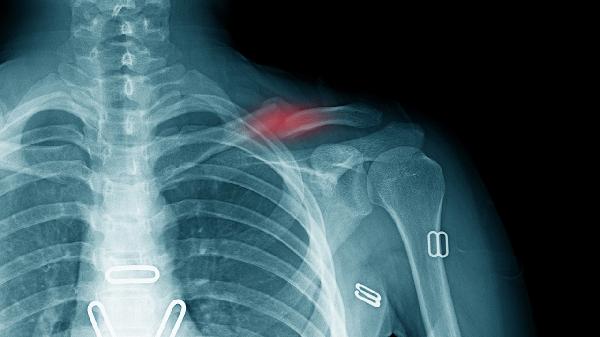

骨质断裂和骨折属于同一概念的不同表述,通常骨折更严重。骨折指骨骼完整性和连续性中断,可能伴随血管神经损伤或移位;而骨质断裂多用于描述轻微骨裂或未移位的稳定性骨折。

骨折根据损伤程度可分为闭合性骨折和开放性骨折。闭合性骨折皮肤完整,软组织损伤较轻,常见于跌倒或撞击。开放性骨折皮肤破损,骨骼暴露,易继发感染,多由高能量创伤导致。骨折还可能伴随明显移位,需手法复位或手术固定。严重骨折可能损伤周围血管神经,影响肢体功能恢复。

骨质断裂通常指裂纹骨折或青枝骨折,常见于儿童或骨质疏松患者。这类损伤骨骼未完全断开,无明显移位,通过石膏固定可自愈。骨质断裂疼痛肿胀较轻,康复时间较短,较少出现并发症。但若发生在承重骨如股骨颈,仍需警惕潜在移位风险。